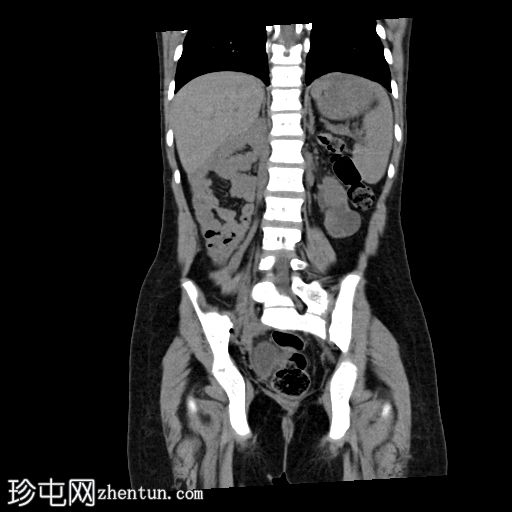

冠状位

平扫

胰体和胰尾未显影,仅胰头显影,可能为背侧胰腺发育不全所致。

肠袢聚集于右侧肋下区,提示肠旋转不良。

左肾体积较小,肾实质相对扭曲,呈分叶状,可见少量肾实质囊肿。左肾上盏轻度突出。

右肾发育不全。

左髂窝可见边界清晰的低密度影,右侧疑似存在类似结构,可能为异位卵巢。建议行MRI检查以进一步评估。

疑似肾下段下腔静脉(IVC)缺如。